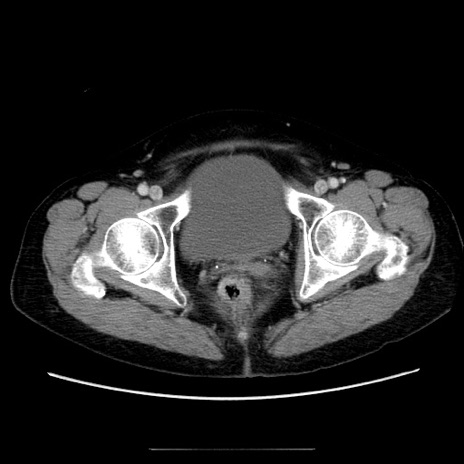

冠状断像

【症例】70歳代女性

【主訴】お腹が張る

【現病歴】1週間くらい前から腹部膨満の自覚あり。昨日夜から増悪したため、本日救急外来受診。

【身体所見】意識清明、BT 36.5℃、BP 165/106mmHg、HR 80bpm、SpO2 98%、腹部:膨満、軟、自発痛・圧痛なし、触診にて不快感あり、腸蠕動音:減弱

【データ】WBC 12600、CRP 1.04